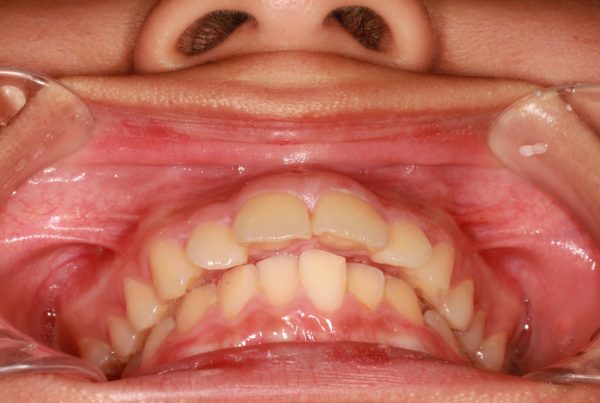

14歳の 女性です

「出っ歯、口もとを 治してほしい」との事で来院されました。

前歯が 飛び出しています。 典型的な ”出っ歯” の状態です

前歯 2本がより前に飛び出ていることが見た目をより悪くしています

前歯が 強く傾斜して、骨ごと 前に 出ています

上顎前突症(いわゆる 出っ歯)です

叢生を伴う 上顎前突症です